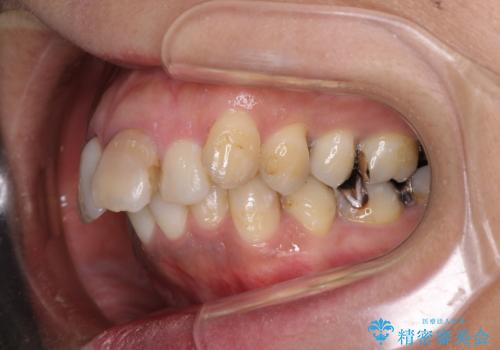

- 歯列全体が内側に倒れ込んでいることと、口元の突出感を気にして来院された患者様です。

上下ともに歯列が狭窄しており、前方に突出している状態でした。

歯が重なるような叢生も認められたため、上下左右の第一小臼歯4本を抜歯して、口元が引っ込むように治療を行うこととしました。

口元を引っ込めることができたため、口を閉じるときに力が入っていて皺のよっていた顎先も、スムーズに閉じられるようになったことで力がかからなくなりました。